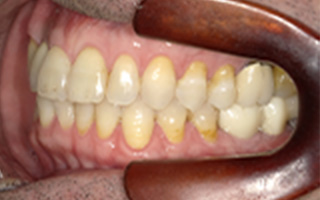

Before

After

| 55歳 男性 | |

|---|---|

| 主訴 | 前歯でしか咬めなく、食事を摂るのに非常に困難で辛い |

| 処置内容 | 上顎6本、下顎3本 |

| 治療費用 | 上顎: 約230万(税込) 下顎: 約120万(税込) |

| 治療期間 | 上顎: 1年(仮歯まで8ヶ月) 下顎: 8ヶ月(仮歯まで5ヶ月) |

| リスク | 上部構造物、仮歯の破折、術後の腫れ(3日)、人工歯根脱落リスクがあります |